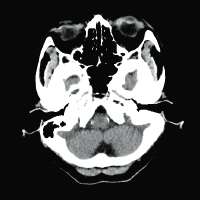

Для снижения лучевой нагрузки и повышения качества визуализации в КТ SUPRIA используются алгоритм интеллектуального перераспределения дозы IntelliEC и современный метод итерации IntelliIP, позволяющие провести сканирование с очень низкими значениями доз и получить изображения необходимого диагностического качества. В результате лучевая нагрузка на исследуемую область существенно снижается при сохранении высокого качества визуализации, особенно на уровне плотных паренхиматозных органов.